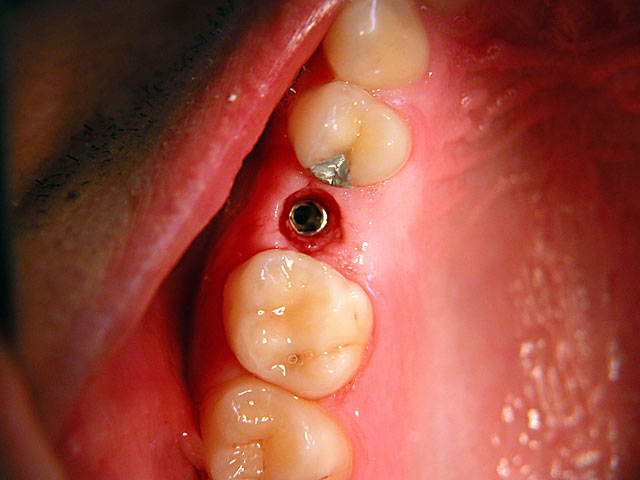

Die folgenden Patientenfälle sollen Ihnen einen Einblick in die Möglichkeiten der modernen Implantation geben.

Sofort-Implantation:

Implantation – Patientenbeispiel 2: